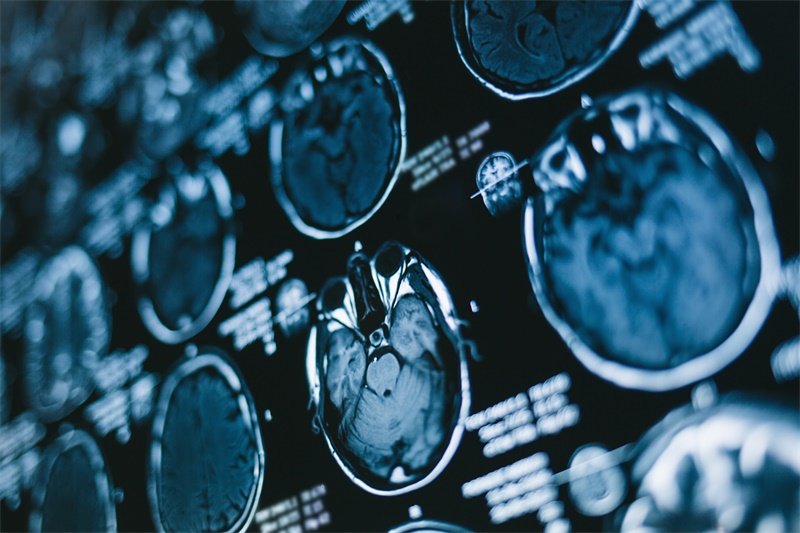

MRI特征

磁共振成像(MRI)是诊断顶枕部大脑镰旁占位病变的主要工具。影像学检查可帮助识别病变的形态、大小及其与周围组织的关系。

在MRI影像上,不同类型的病变呈现出不同的特征,例如肿瘤可能显示出明显的边界和异质性,而血肿可能会伴随高信号强度。

CT特征

计算机断层扫描(CT)也可用于初步评估。CT影像可显示病变区的密度变化,帮助判断病变的性质及急性期的处理。